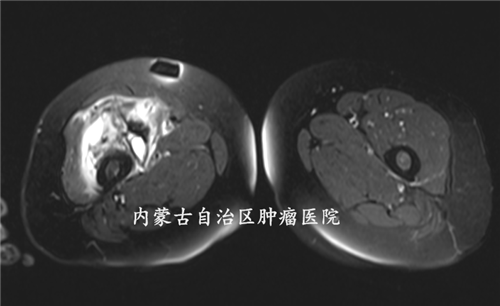

| 患者女,58岁,主因“发现右大腿恶性肿瘤、疼痛半年余”入院。患者半年前触及右大腿长一肿物,约鸡蛋大小,间断疼痛,未重视。肿物进行性增大,2019年10月31日就诊于当地医院,行肿物穿刺活检,病理回报提示:高级别间叶源性恶性肿瘤,于2019年11月、2019年12月、2020年1月行顺铂、表柔比星、异环磷酰胺抗肿瘤化疗。近期疼痛加重,现就诊于我院骨科门诊,以“右大腿恶性肿瘤、3周期化疗后”收入院。患病以来,患者一般情况尚可,饮食可,睡眠欠佳,二便正常,体重无明显变化。 |

| 专科查体:右大腿前侧可见长约5cm横行切口瘢痕,皮下可触及圆形输液港。右大腿较左大腿明显肿胀,右大腿前方可触及巨大肿物,边界尚清,压痛阳性,皮温不高,肿物活动度差,大小约20cm*10cm,右膝关节、右髋关节活动尚可。右下肢肢端血运及感觉正常,肌力正常。余肢体未见明显异常。 |

术前诊断:右大腿恶性肿瘤、3周期化疗后